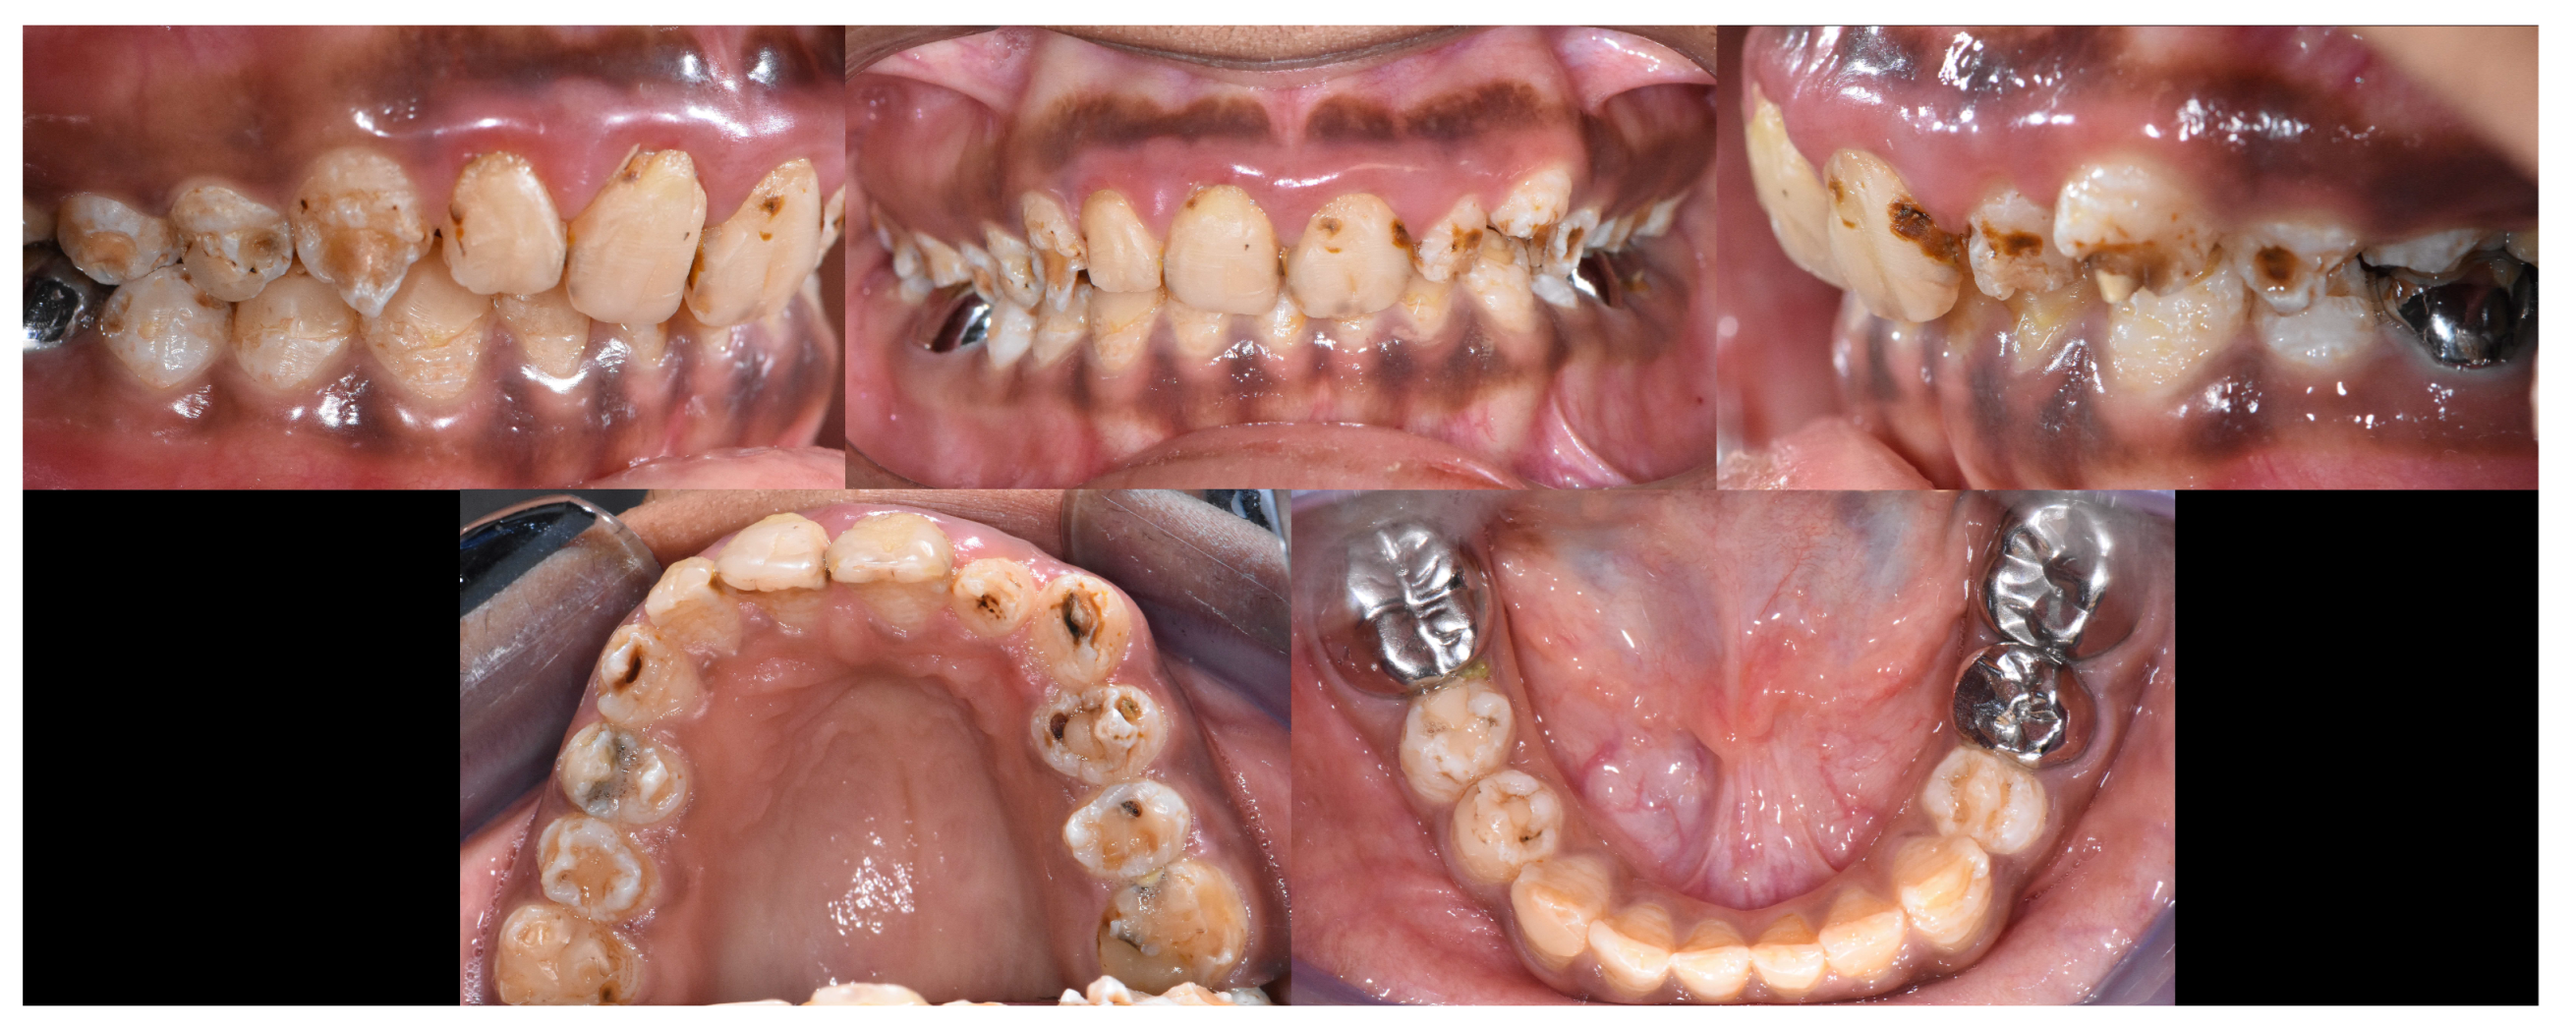

2.2. Clinical Examination

2.3. Radiographic Examinations